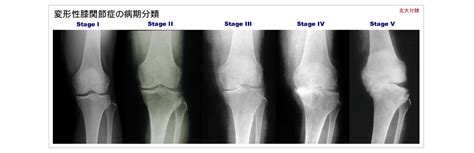

平成28年8月27日に行われた第31回市民医療講演会の模様が、catvいなばぴょんぴょんネットにて放送されました。講演1 「変形性膝関節症について」 整形外科 岡田 幸正講演2 「膝の痛みを和らげる体操」 リハビリテーション部 山根 伸亮. Manage your video collection and share your thoughts.